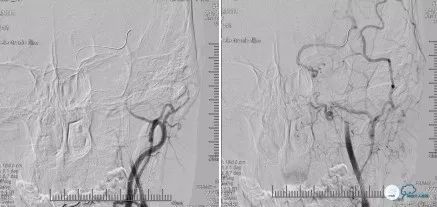

沿Transend微导丝送入自膨式Wallstent(7mm*50mm 135cm)支架,支架头端至左颈内C1远端,准确定位后释放支架(图15)

再次造影提示:支架内血流通畅,左颈C3至C4段显影浅淡,晚期左侧大脑中动脉显影,考虑海绵窦段闭塞血管,球囊扩张不充分,管壁仍有塌陷,造成血流不通畅(图16)

遂沿Transend微导丝送入Tazuna球囊(2.5*20mm),沿左颈内C4至C2段由远及近重叠扩张狭窄血管(图17)

再次造影提示左侧大脑前动脉显影,但左颈C3至C4段仍显影浅淡,考虑海绵窦段血管局部仍有弹性回缩(图18)

静脉替罗非班8ml缓慢静脉推入,并经球囊Guiding导管动脉推入4ml替罗非班。沿Transend微导丝送入Select导管及自膨式Enterprise(4.5mm*37mm)支架于左颈内动脉C4段,准确定位后缓慢释放(图19)

撤出Select导管,再次手推造影提示支架贴壁欠佳,遂再次沿Transend微导丝送入Tazuna球囊(2.5*20mm)扩张Enterprise(4.5mm*37mm)支架,再次手推造影提示左侧大脑前显影,前交通开放,但左颈内动脉C3段显影浅淡(图20)